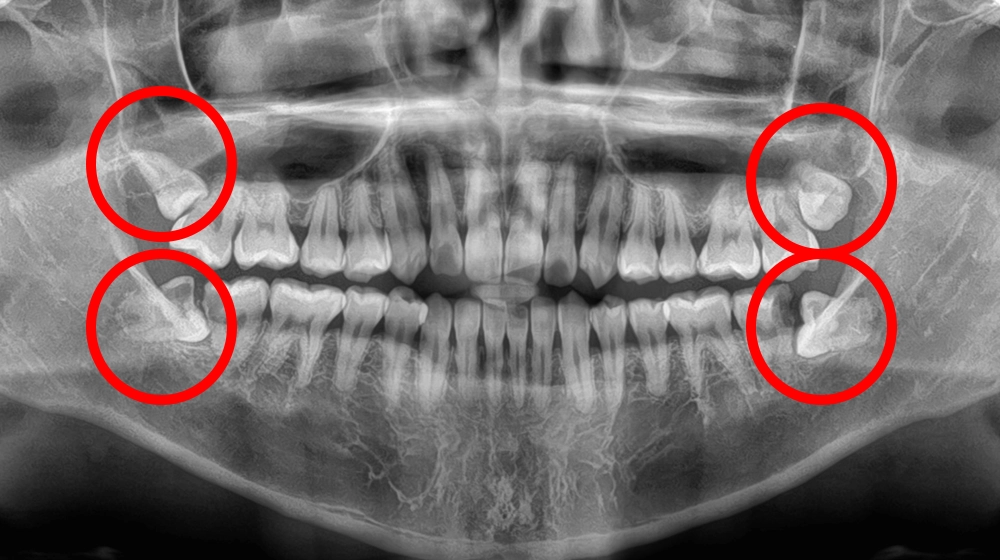

歯茎に埋まっている

親知らず抜歯

歯茎に埋まっている親知らずイメージ

費用(1本) 約4,000〜5,000円

抜歯時間 約10〜30分